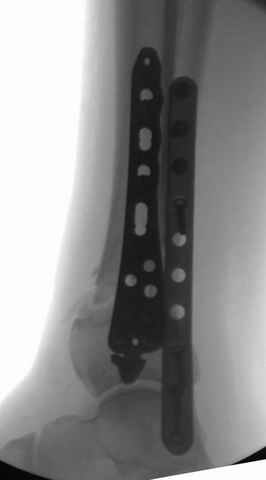

На снимках варианты фиксации малоберцовой:

№ 2-5 при огнестрельном переломе